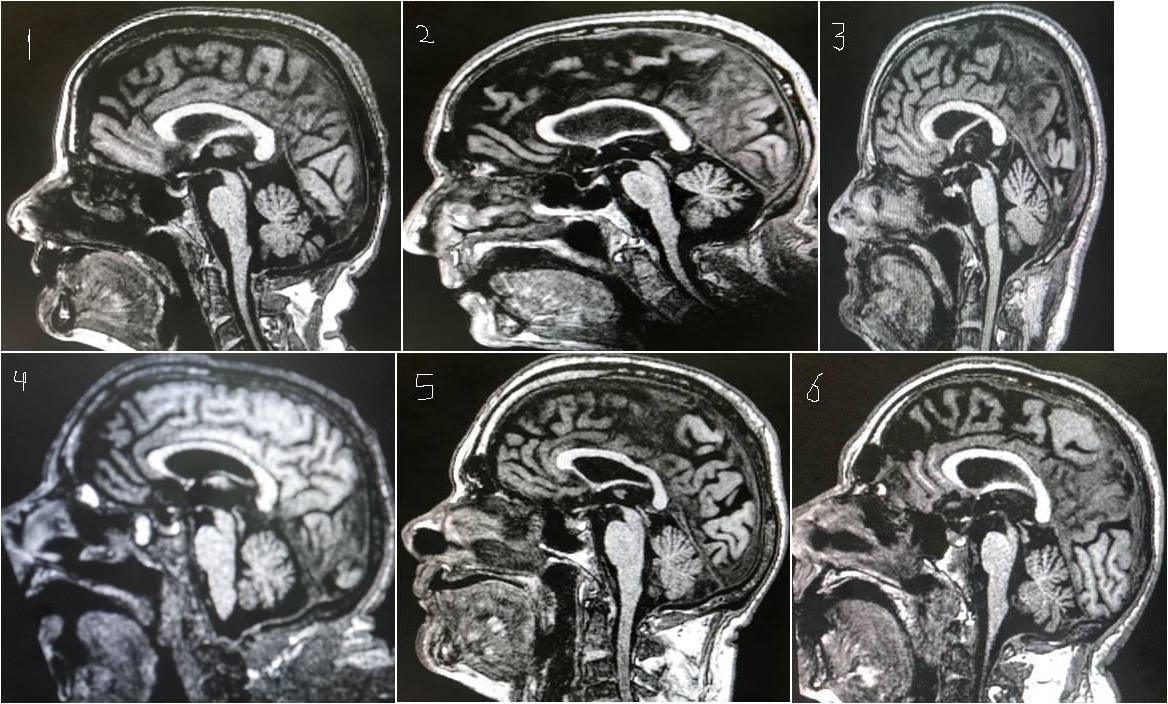

From www.researchgate.net

Tauopathies. Upper row PSP (a) medial view of the left cerebral What Is Psp Brain Disease psp is a rare neurodegenerative disease caused by the progressive death of nerve cells in certain parts of the brain. progressive supranuclear palsy (psp) is a rare neurological condition that can cause problems with balance, movement, vision, speech and. progressive supranuclear palsy can cause changes in your brain that make you feel anxious or laugh or cry. What Is Psp Brain Disease.